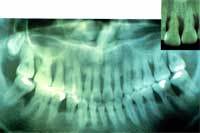

健康な歯槽骨

歯周病で退縮した歯槽骨